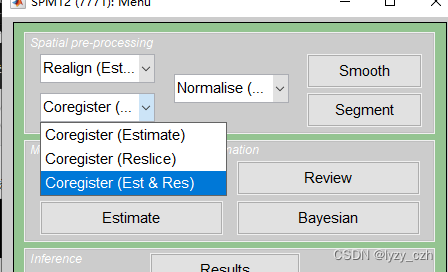

4)将wmeanxxxx.hdr配准到自己的MRI图像wmxxxx.nii上,打开Coregister(Est & Res),只修改Reference Image和Source Image;

注意:如果只需要处理PET图像,MRI可以使用模板来进行配准和去头骨影像(这里是配准到同一患者的SMRI预处理后的图像 wmxxxx.nii是SMRI预处理后的图像)